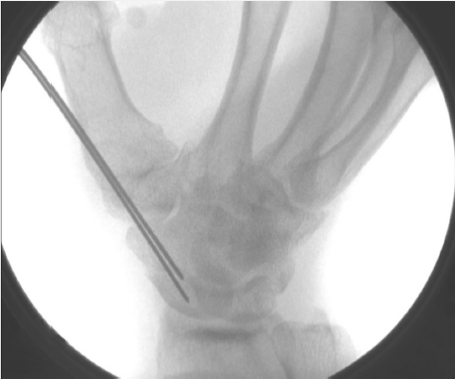

After appropriate alignment has been obtained and a central K-wire has been placed for a cannulated screw, it may be useful to place a second K-wire, eccentrically across the fracture site as an antirotation pin prior to screw insertion. Alternatively, if the first pass of a K-wire ends eccentrically, this should be left in place as an additional visual cue to place a second K-wire centrally and the first will take on the function of an antirotation pin (► Fig. 41.4).